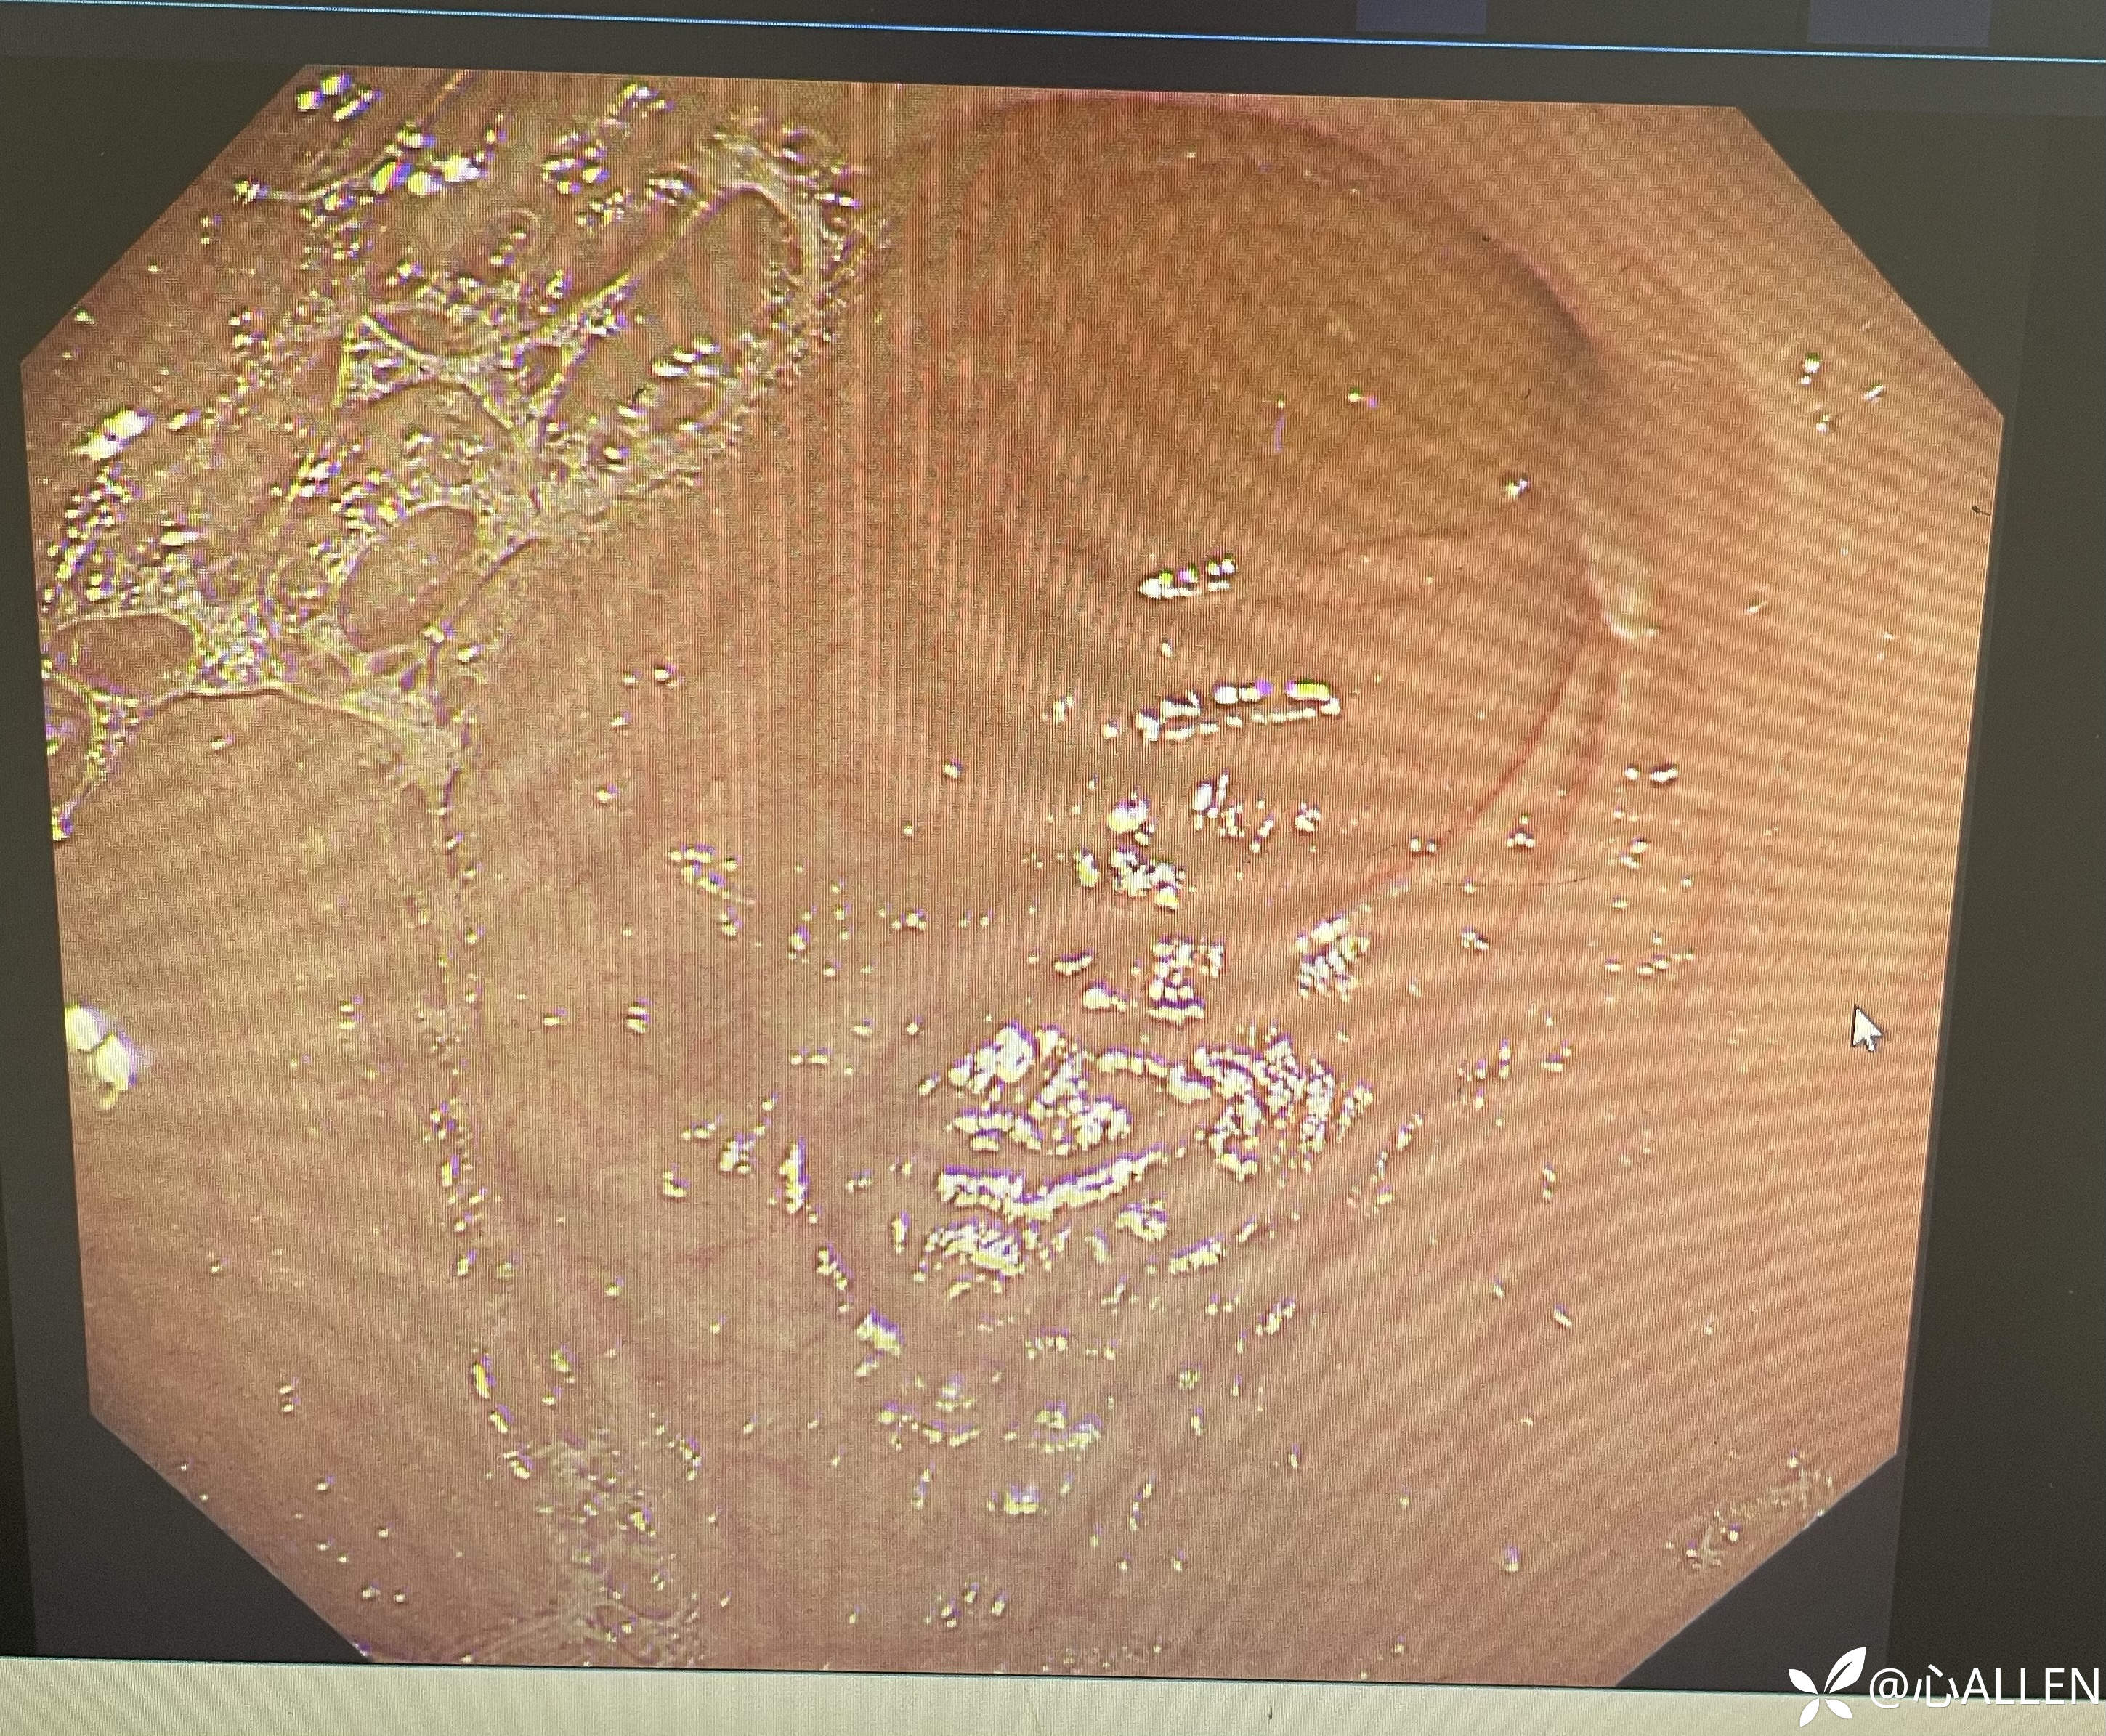

胃窦及幽门

进镜观察到扩大的球腔,远端似有主乳头